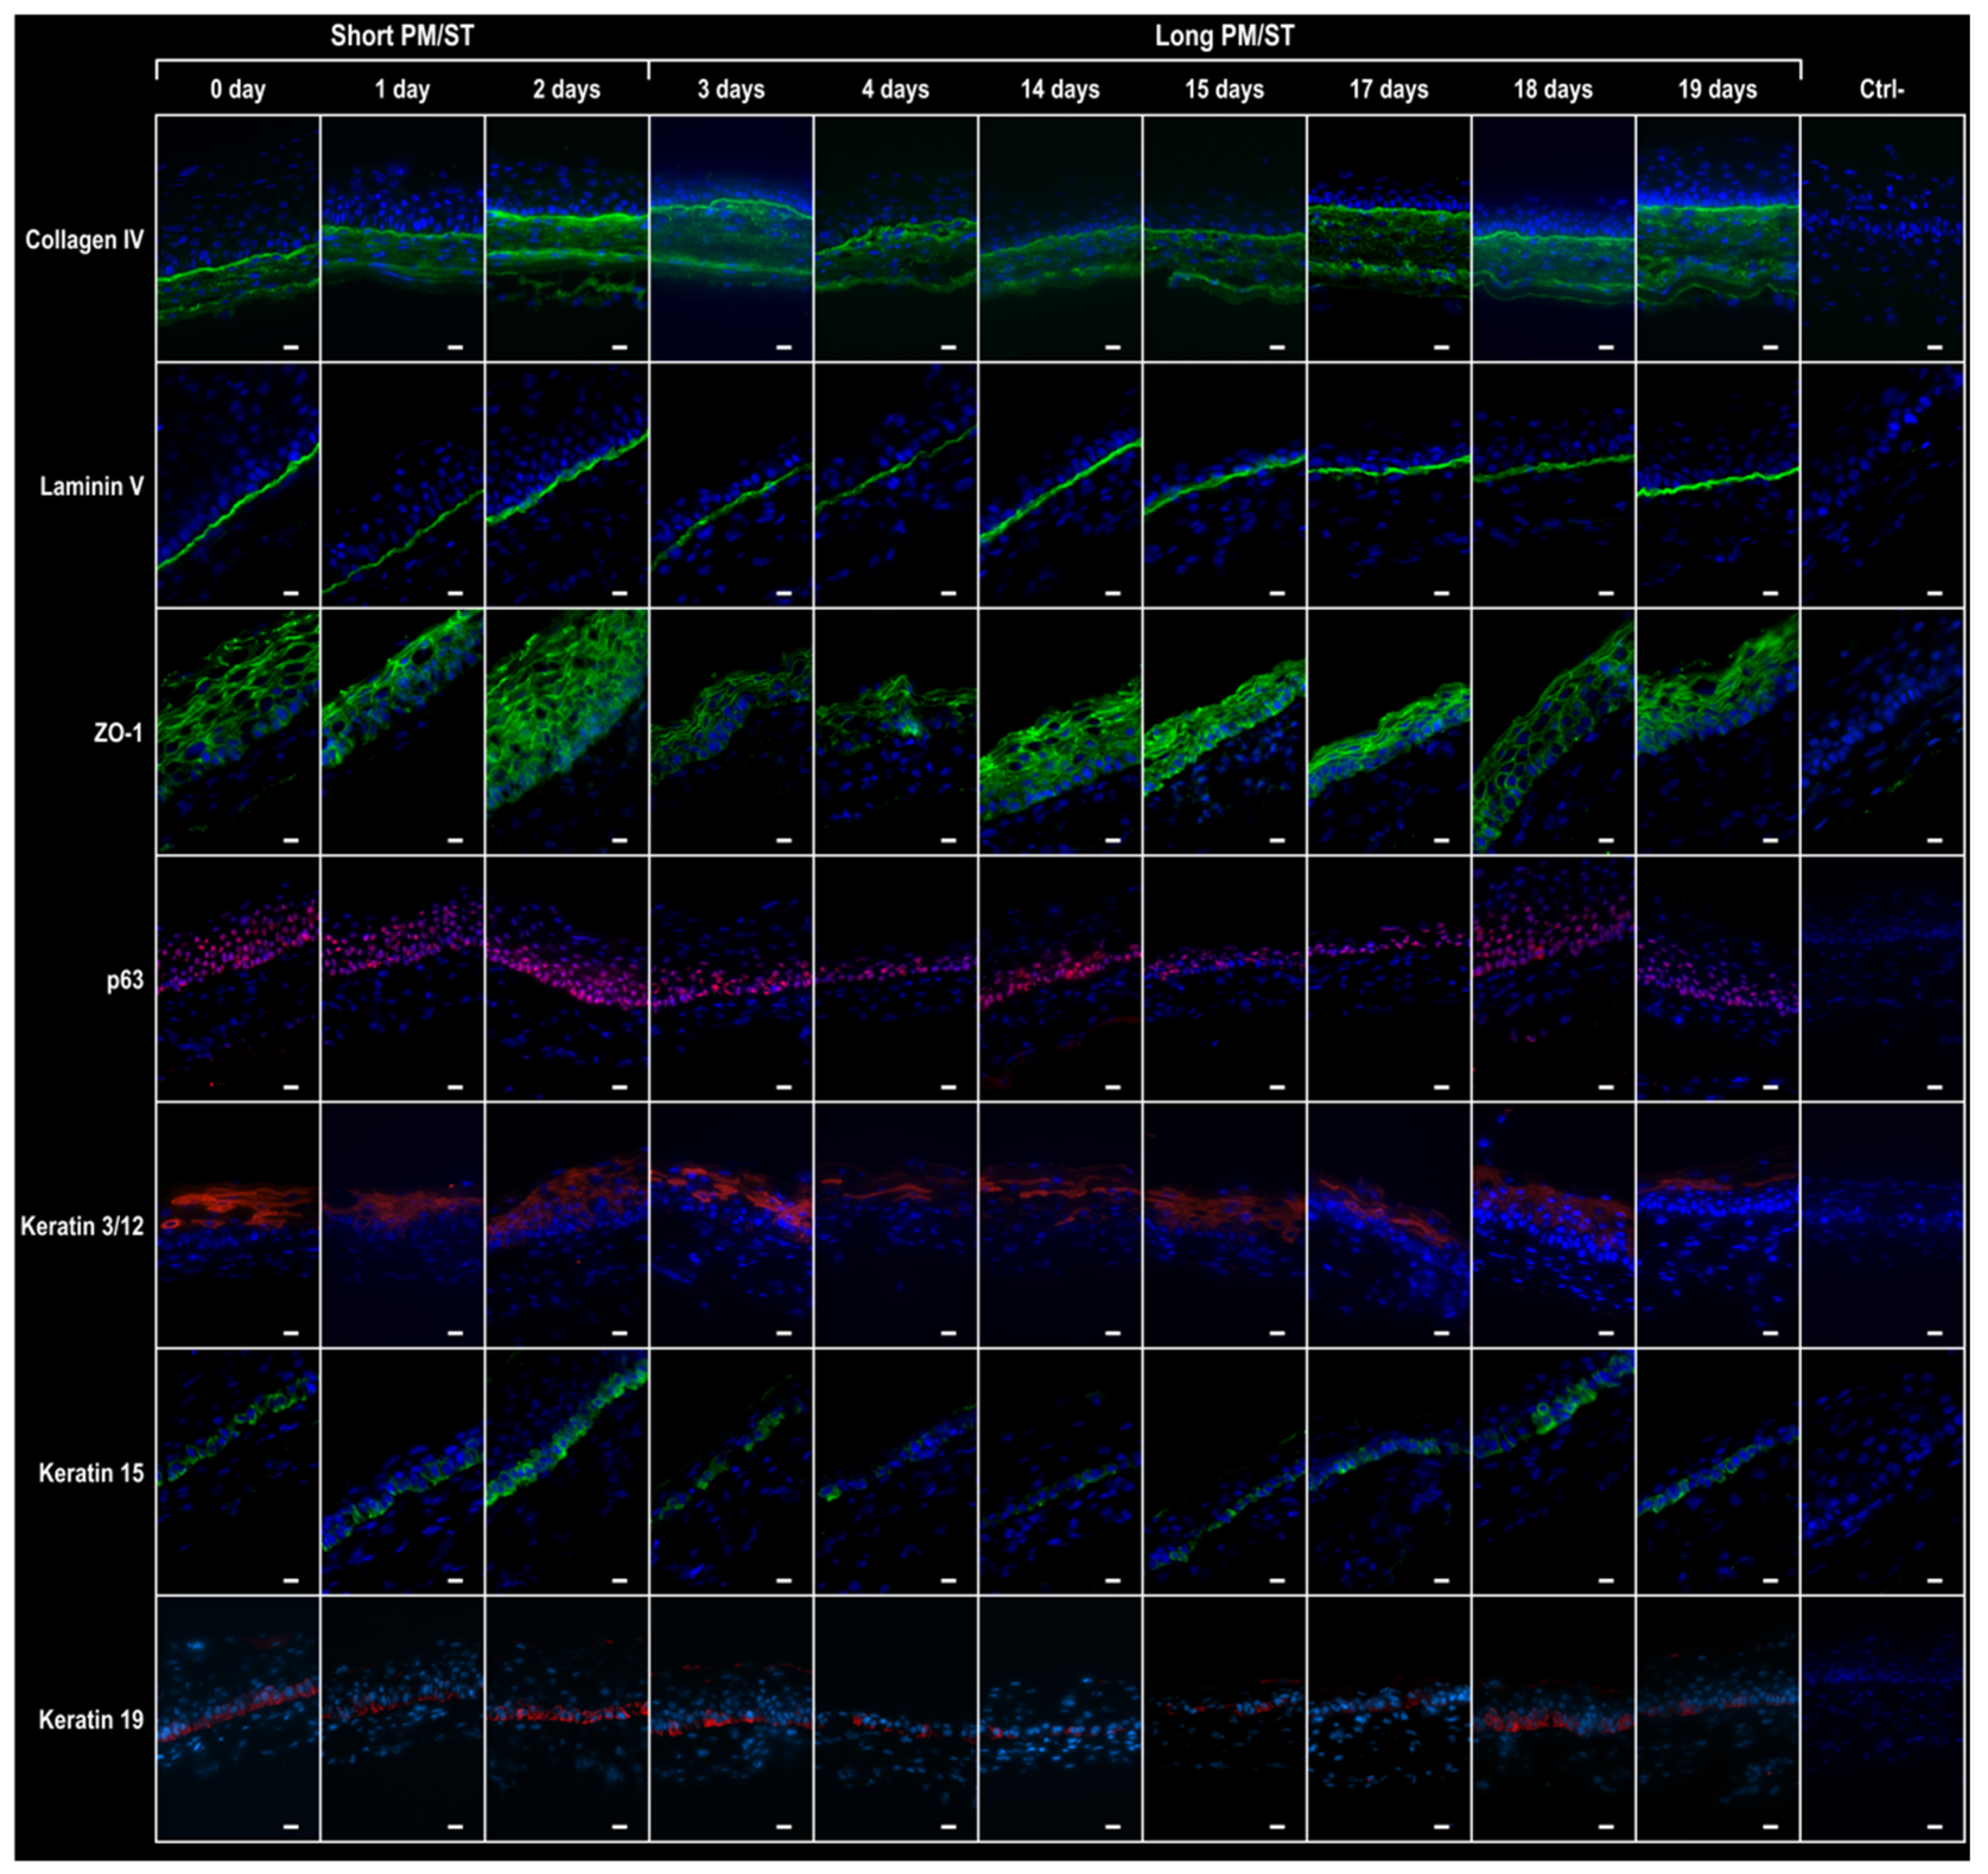

3.6. Integrity of the hTECs Produced Using Short and Long PM/ST hLECs

3.7. Wound Closure Dynamic of hTECs Produced Using Short and Long PM/ST hLECs